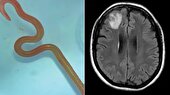

تصادف یا هر حادثه دلخراشی که به بدن انسان ضربه وارد کند، معمولا به‌سختی از ذهن افراد پاک می‌شود اما آنچه غیر از خاطره‌ای دردناک و دلهره‎آور، زندگی شخص را تحت تاثیر قرار می‌دهد، محدودیت‌های حرکتی ناشی از آسیب‌های نخاعی است که امکان دارد تا مدت‌ها باقی بماند. برخی بیماری‎ها مانند ام‌اس هم تجربه‌ای مشابه را در محدودیت‌ فعالیت اندام‌های حرکتی برای افراد رقم می‌زند؛ اتفاقی تلخ که شاید از نگاه بسیاری، پایان استقلال فرد باشد.